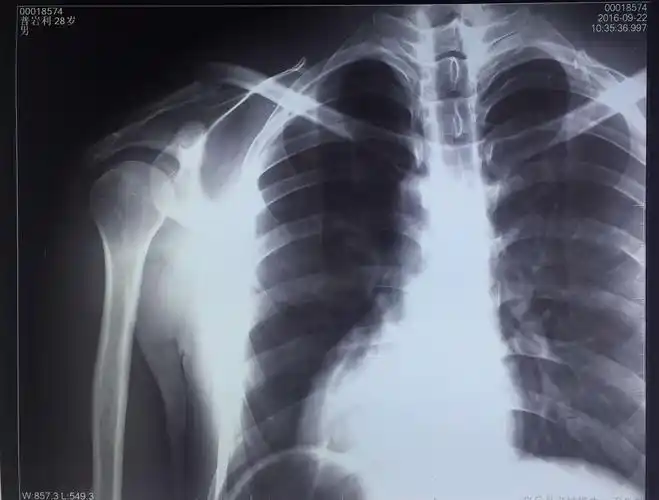

右锁骨中段骨折